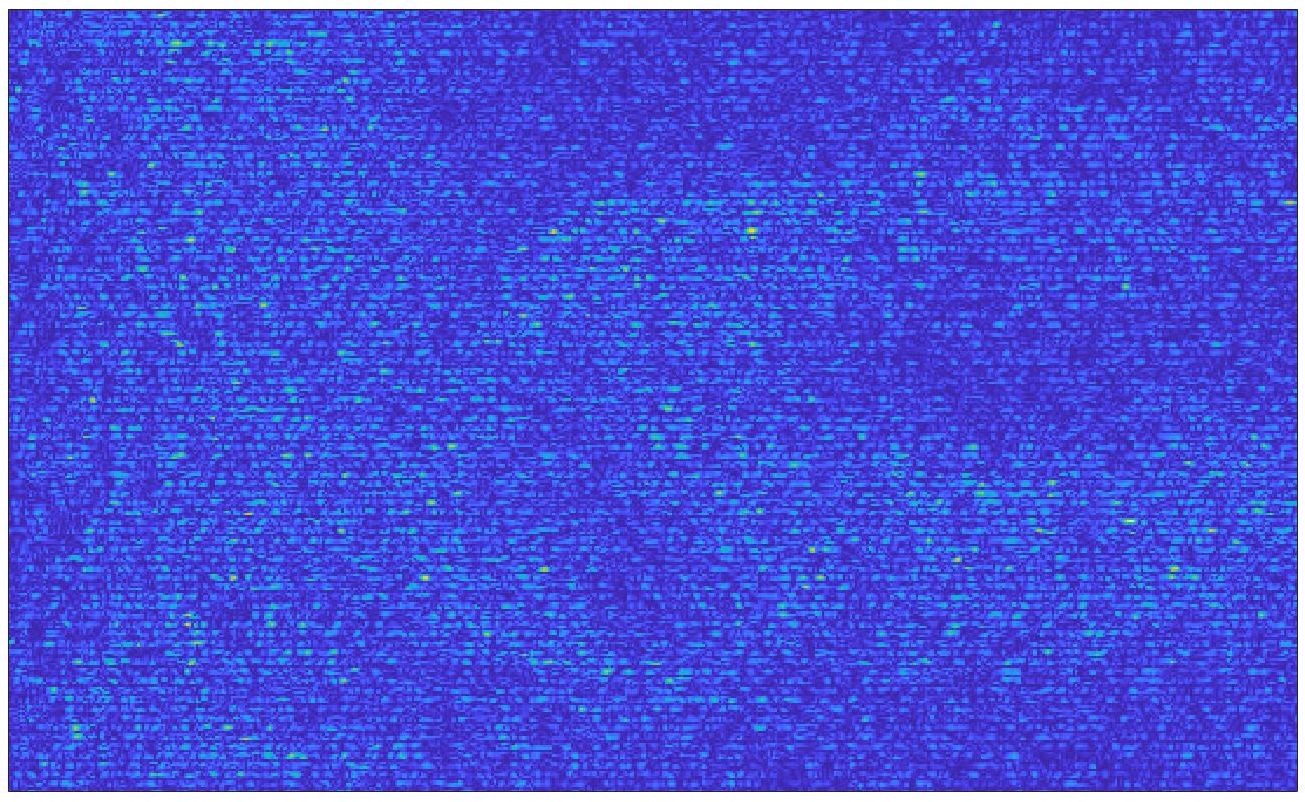

We train each learning-based network (custom-WDSR) with 1.5K images, where the input is the outcome of the selected up-sampling method (i.e., Cubic convolution), and the target is the original high-resolution image. Indeed, input and target images have the same resolution, as the reconstruction of the missing lines has been already performed by Cubic convolution. Figs. 3, 4, and 5 show the results of the network prediction, compared with the input and the target images. Target images correspond to spatial high-resolution images; input images are the outcome of the up-sampling interpolation, which is applied to spatial low-resolution images (i.e., the down-sampling along the lateral direction of high-resolution images); prediction images represent the output of the neural network.

Our framework visually improves the results, in terms of blurring and artefacts. This result is more evident in the magnification of the ear of the foetus (Fig. 3), the mitral valve (Fig. 4), and the mass edges (Fig. 5). Fig. 6 shows the error image of the three anatomical districts with both 2X and 4X up-sampling factors, with the maximum error in the scale . The error is more evident in the contours of the anatomical structures; moreover, the abdominal district shows a smaller error than the cardiac and obstetric ones. We underline that the view for each image is scaled to its maximum, to improve the visualisation of the error.

| 2X | 4X |

| Max. error: 18 | Max. error: 35 |

|

|

| Max. error: 33 | Max. error: 62 |

|

|

| Max. error: 40 | Max. error: 80 |

|

|

| Max. error: 41 | Max. error: 75 |

|

|

| Max. error: 12 | Max. error: 22 |

|

|